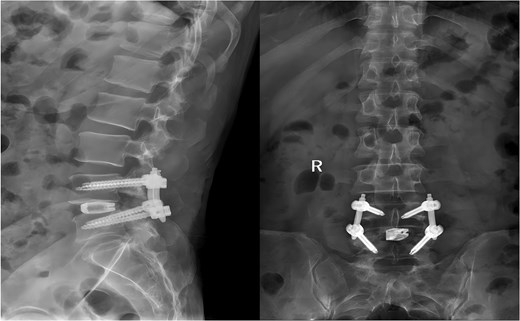

A 49-year-old male presented with a 10-month history of low back pain accompanied by numbness in the left lower limb. Over the past 2 weeks, his symptoms had progressively worsened without any identifiable precipitating factor, with increasing pain and numbness radiating down the left lower extremity. The patient reported that walking about 20 meters aggravated his symptoms, which were relieved after rest, allowing him to walk another short distance before the pain recurred. Due to the lack of significant relief from over-the-counter analgesics and topical medications, he presented to our outpatient clinic for further evaluation. Clinical examination and preoperative imaging demonstrated lumbar spinal stenosis at the L4/L5 level, lumbar instability, and grade I spondylolisthesis at L4 (Fig. 1). Following a comprehensive preoperative assessment, the patient was scheduled for PE-PLIF.

Preoperative anteroposterior and lateral radiographs of the lumbar spine.